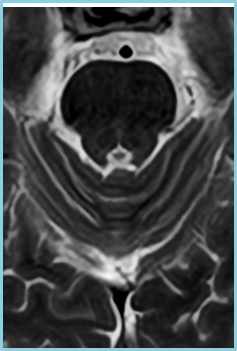

在磁共振领域,深度学习技术对图像进行降噪、上采样、减轻振铃伪影的处理,带来了清晰且细节丰富的图像。

过去,高分辨率图像的获取往往伴随着漫长的扫描时间,这影响了图像获取的效率,对于危重疾病的快速诊断是一大挑战。然而,PIQE技术的出现彻底颠覆了这一局面。此次发布的全新3T磁共振Galan Supreme,搭载全新的自研磁体和梯度线圈,并深度融合PIQE技术,可以实现在不增加扫描时间的前提下,轻松获取到高分辨率的图像,为临床带来了兼具高效与高质量的影像体验。

左右滑动查看更多